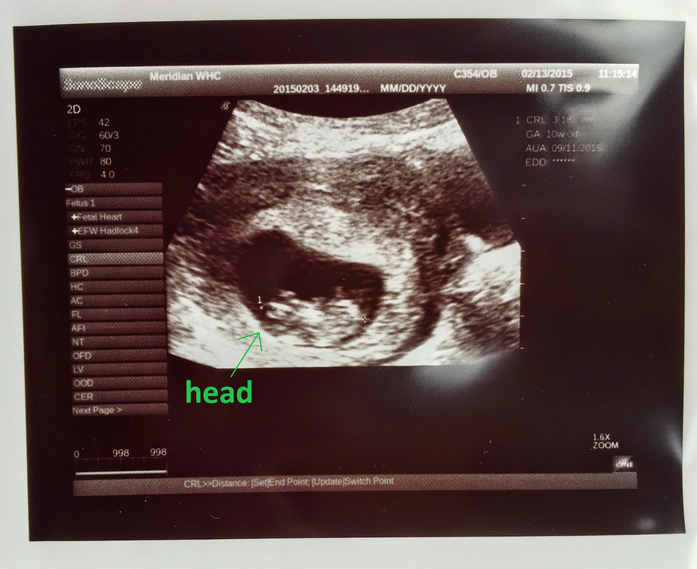

I had my first ultrasound last Wednesday. I went in thinking I was 9weeks 6days (this was based off my last cycle) but after they measured the baby they said I was 10weeks 6 days. I can't stop looking at my baby. I'm a FTM also.

Oh I'm so excited to post! Had a mini scare over the weekend and went in for a super quick scan yesterday to make sure everything was ok! It was Great actually! Heard the little ones heartbeat for the 1st time - AMAZING. Here (s)he is at 10 weeks 6 days.